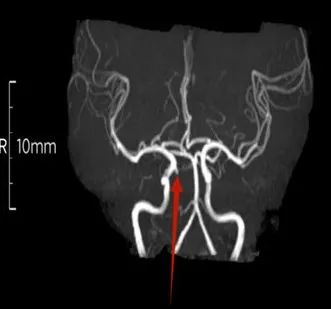

该项技术通过最大密度投影(MIP)法还能够清晰呈现患者头颈部动脉血管与周围组织的空间关系,可发现血管狭窄和闭塞的部位,对软斑块纤维帽有优势,对有无血栓及出血性疾病、脑动脉瘤和脑血管畸形进行初步诊断和评估。

患者李女士,女,44岁,反复头晕2年多,在我院行头颈联合3D-TOF-MRA筛查,发现右侧颈内动脉C7段2.5mm微小动脉瘤。